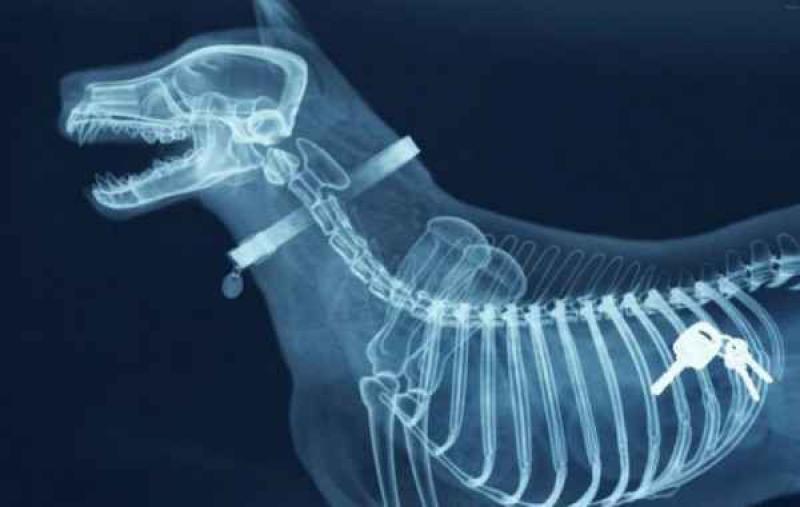

Röntgenfoto's zijn een medische uitvinding die ons al decennia lang helpt. Ze geven een nieuw gezichtspunt als het gaat om het vinden en behandelen van inwendige verwondingen. De machines kunnen opmerkelijke beelden vastleggen van het menselijk lichaam en ze documenteren vaak gruwelijke verwondingen. Een wonde van iemand zien, is al erg, maar als je ook kan zien wat de schade in het lichaam is, dat is nog veel erger. We hebben 12 tegelijk fascinerende, gruwelijke en hilarische röntgenfoto's op een rijtje gezet. Stel jezelf maar eens de vraag hoe iemand ooit aan die verwondingen is gekomen. We beginnen nog rustig.